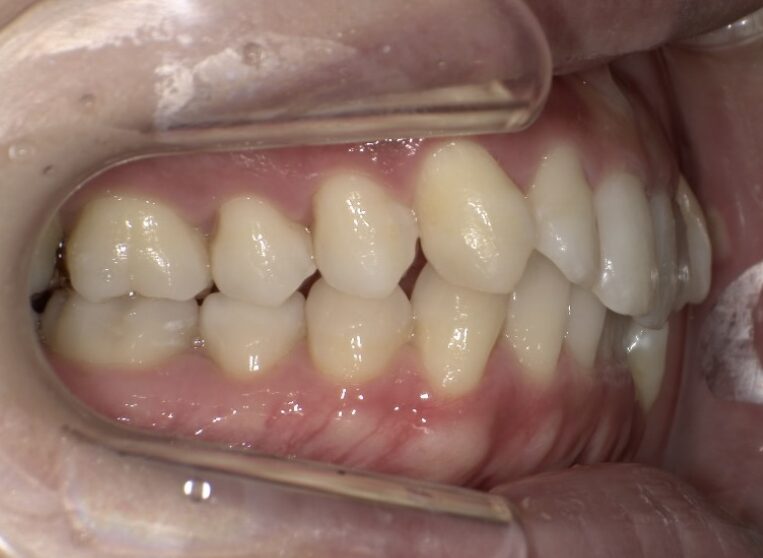

治療経過(半年後)

治療開始から半年ほどで、前歯の重なりは徐々に改善し、清掃性も向上してきました。患者さま自身も「磨きやすくなった」と実感されています。